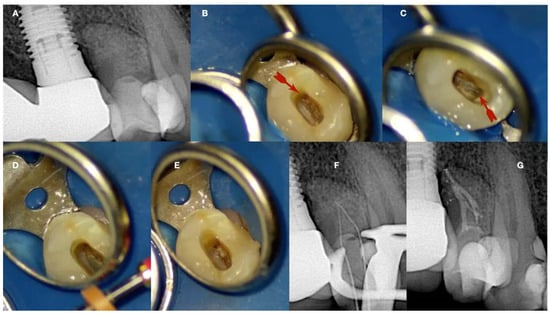

Figure 9.

(A) Radiographic image of an extracted partially calcified maxillary premolar. (B) Magnified view at the level of the axial cut (a grey area in a). (C,D) Creation of initial access dimple in the white spot indicating the calcified orifice. (E) Continuous chelation of the cut dentinal surface (F,G). An initial unsuccessful attempt to negotiate the calcified canal orifices with D-finder files iso 08. (H) Fitting of the tip of an EDM file (Hyflex EDM-one file, Coltene) in the dimple without activation. (I,J) On-spot buckling resistance activation test (BRAT) negotiation of the EDM files. (K) Negotiation of the 08 d-finders inside the calcified canals after the BRAT negotiation technique removed coronal calcified canal obstructions. (L) Radiographic verification of calcified canal negotiation (images and radiographs courtesy of Dr. Chaniotis Antonis).

The initial dimple is deepened progressively in a crown-down sequence until a patent pathway is met and confirmed (Figure 9 and Figure 10).